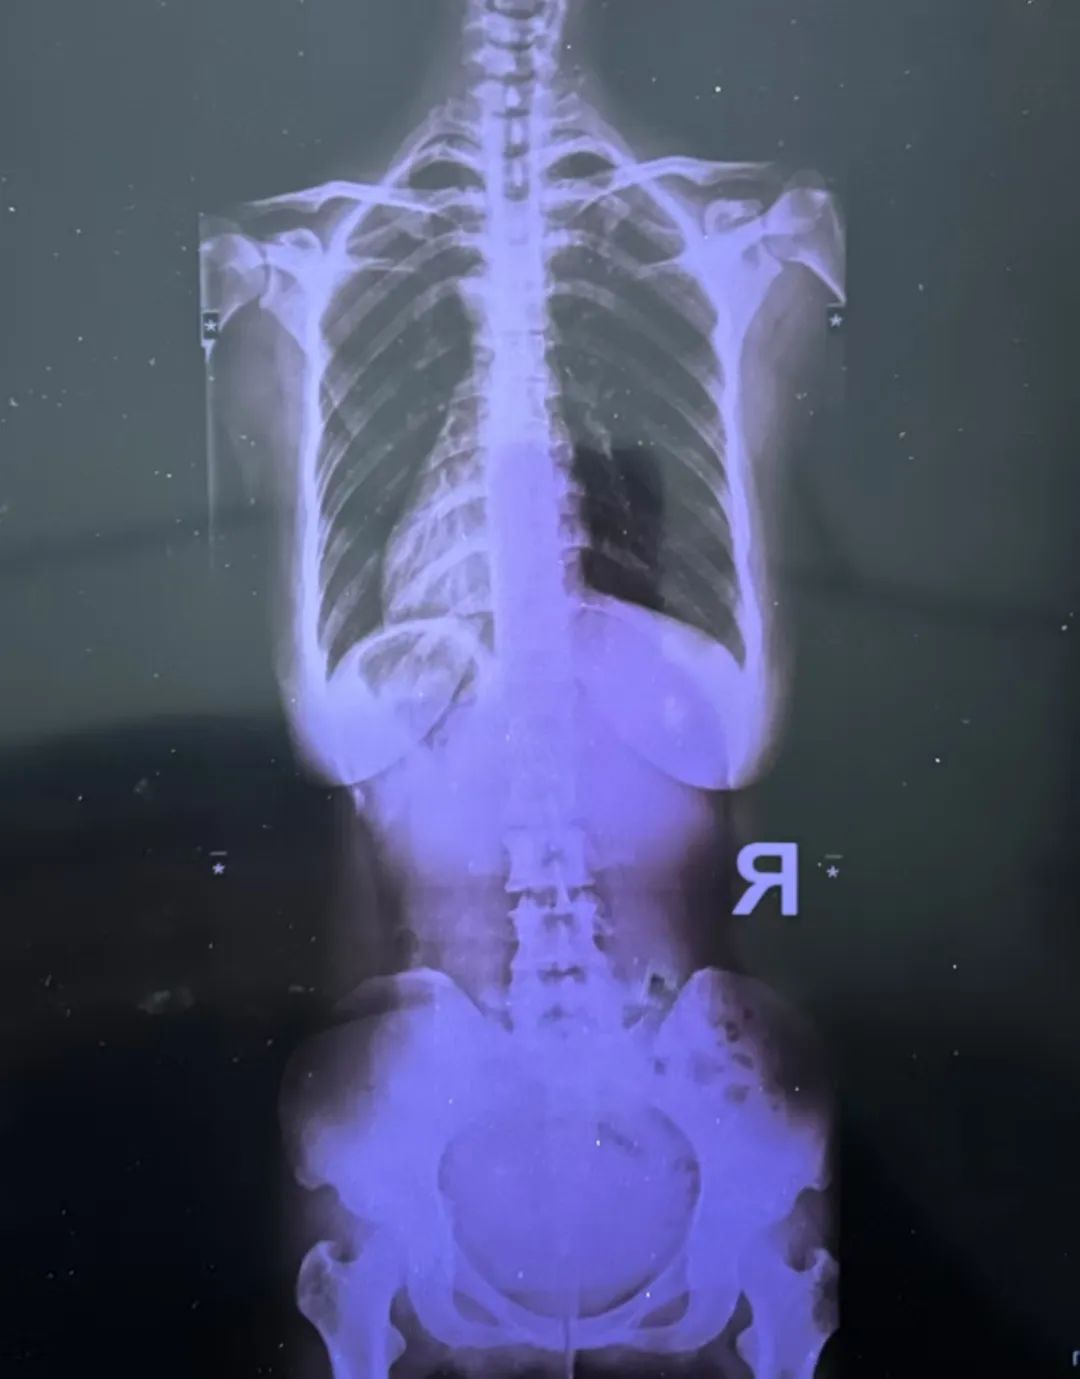

最近又疼起來嚴重影響正常生活,她前往醫院就診,結果查(cha)出了脊柱(zhu)側彎11°,骨盆旋移,骶髂關節半脫位,由(you)于這些導致頸肩,后背(bei),腰部肌群代償出現(xian)問題,從而出現(xian)腰痛,后背(bei)痛,肩膀痛!

蘇鴻凱醫生根據王女(nv)士的具體情況,為(wei)王女(nv)士制(zhi)定針對性治(zhi)療(liao)方(fang)案,在治(zhi)療(liao)中采用正骨(gu)手法復(fu)位,在配合結構(gou)針法治(zhi)療(liao),來調節肌肉功能(neng)使(shi)恢復(fu)平衡。